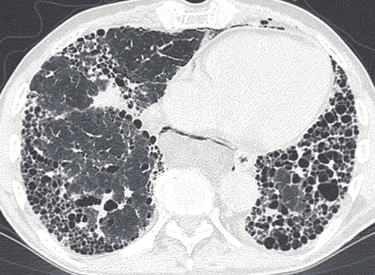

Następnie skierowałem swoje zainteresowania w kierunku pulmonologii – egzamin specjalizacyjny zdałem w 2012 roku pod kierownictwem Pana Profesora Dariusza Ziory w Klinice Chorób Płuc w Zabrzu, gdzie później pracowałem pogłębiając wiedze i doświadczenie szczególnie w diagnostyce i leczeniu chorób śródmiąższowych, co jest moim szczególnym zainteresowaniem.

Aktualnie kieruję dużym blisko 70 łóżkowym oddziałem chorób płuc i gruźlicy w pilchowickim Szpitalu Chorób Płuc. Zajmuję się endoskopową ( bronchoskopia, EBUS) diagnostyka chorób płuc, w tym nowotworowych. Diagnostyką śródmiąższowego włóknienia płuc i kwalifikacją do leczenia w ramach programu lekowego – IPF w naszym oddziale. Od ponad 15 lat prowadzę poradnie domowego leczenia tlenem stąd zajmuję się oceną i kwalifikacja chorych do leczenia tlenem w domu.

Choroby śródmiąższowe

Opieka nad pacjentami z włóknieniem płuc i sarkoidozą